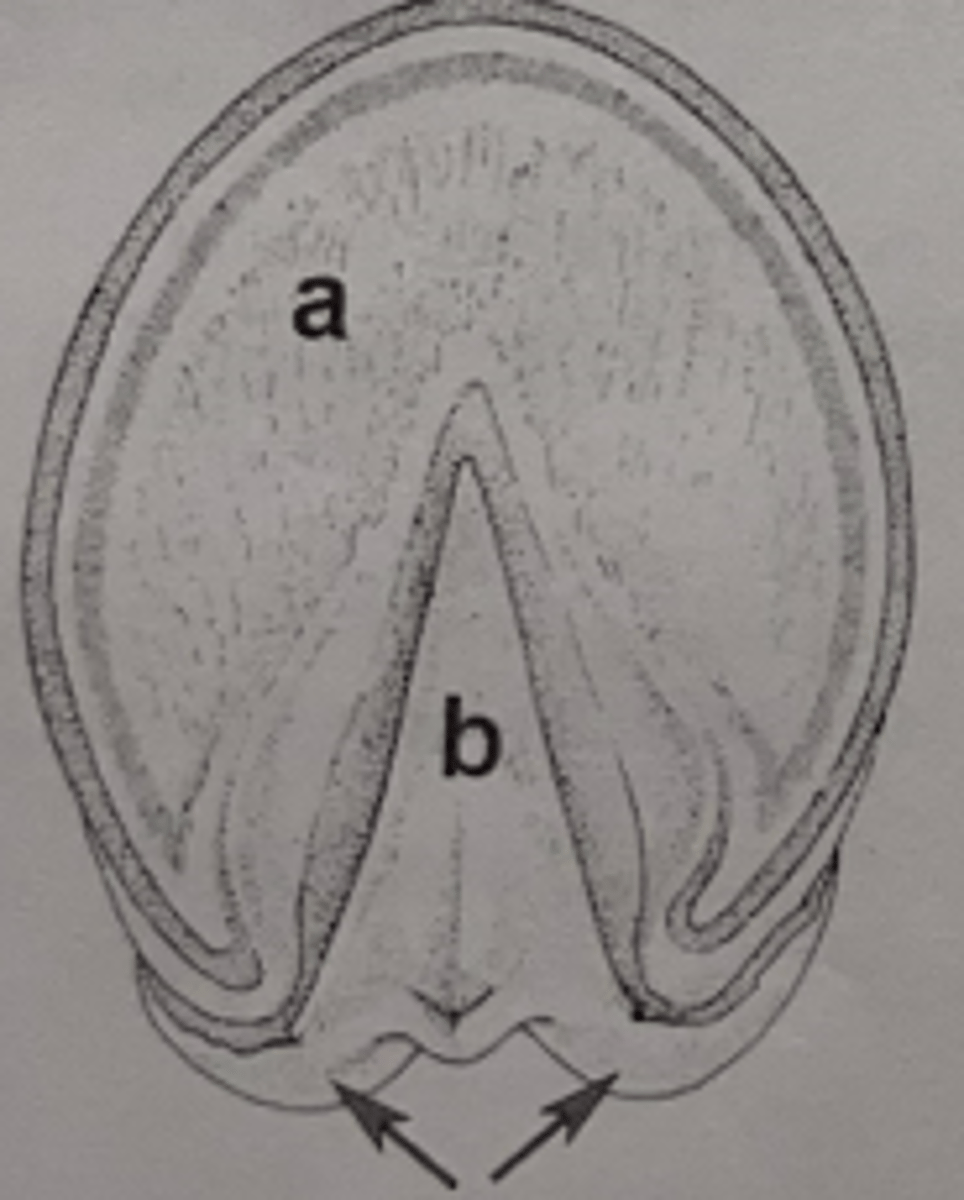

Apex of cecum

What is the name and portion of the organ labeled A?

4

How many bands does structure A have?

Left ventral Colon

What specific segment of the ascending colon is labelled B?

Pelvic flexure

Ingesta leaving section B would go through what flexure next?

What is B?

3 bands in left/right dorsal colon

How many bands does C have?

transverse colon

ingesta leaving C will travel through what impaction site?